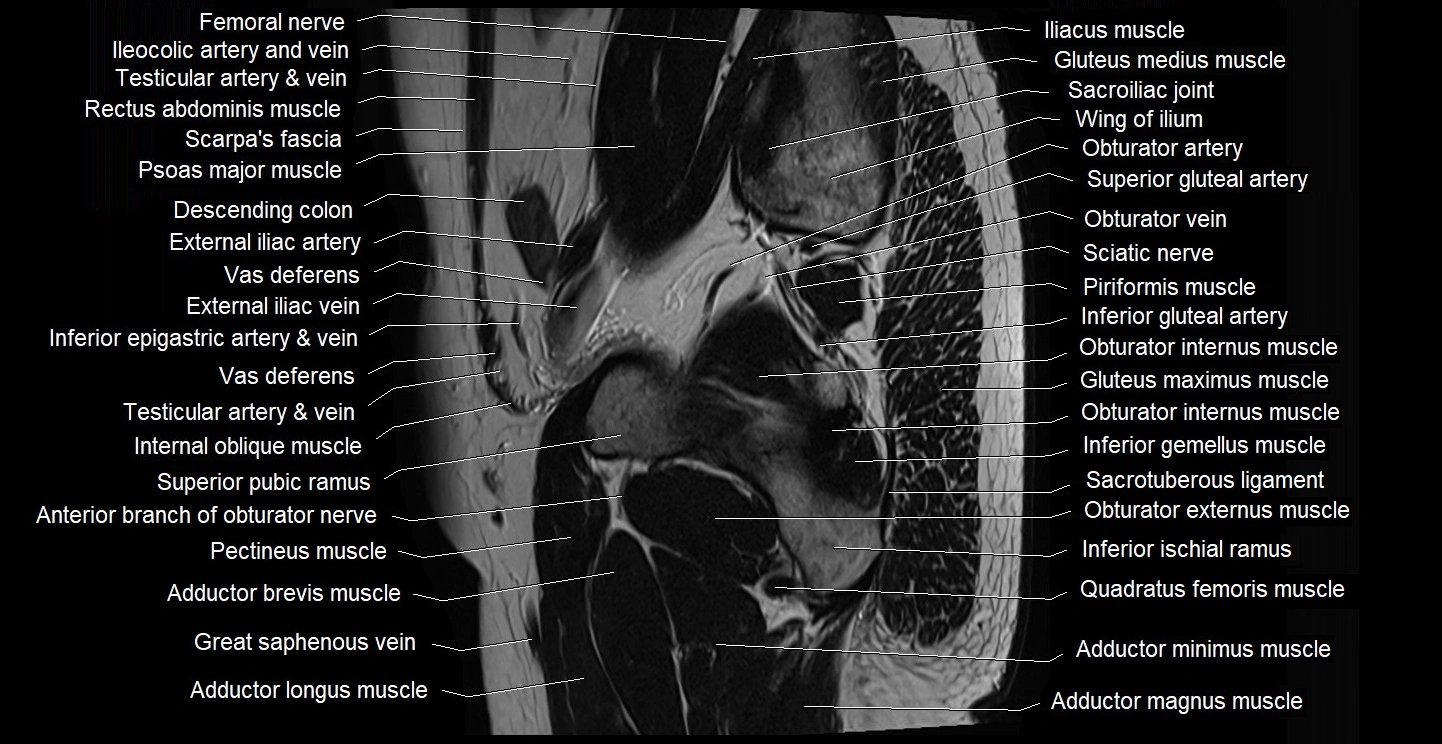

- Adductor brevis muscle

- Adductor longus muscle

- Adductor magnus muscle

- Adductor minimus muscle

- Anterior division of obturator nerve (Anterior branch of obturator nerve)

- Gluteus maximus muscle

- Gluteus medius muscle

- Inferior gemellus muscle

- Inferior gluteal artery

- Obturator externus muscle

- Obturator internus muscle

- Pectineus muscle

- Piriformis muscle

- Quadratus femoris muscle

- Sciatic nerve